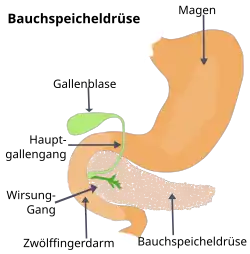

Anatomie

Die Bauchspeicheldrüse ist eine 40 bis 120 g schwere Drüse im Retroperitoneum, hinter dem Magen, links vom Zwölffingerdarm und wird in einen Kopf, einen Körper und einen Schwanz untergliedert. Der Schwanz berührt links Milz und Niere. Der Hauptgallengang durchquert rechts den Kopf der Bauchspeicheldrüse. Die Aorta und mehrere große Eingeweidearterien (Truncus coeliacus, obere Mesenterialarterie, Milzarterie) haben engen Kontakt zur Bauchspeicheldrüse, ebenso die untere Hohlvene und die Pfortader.[10] Alle diese Strukturen können von Bauchspeicheldrüsenkrebs erfasst werden. Die Ausführungsgänge für das Bauchspeicheldrüsensekret (Wirsung- und der beim Menschen nur selten vorkommende Santorini-Gang) verlaufen durch das ganze Organ und können vom Tumor verstopft werden. Ihre Blutversorgung erhält die Bauchspeicheldrüse aus dem Truncus coeliacus und der oberen Mesenterialarterie, manchmal auch aus einer abweichenden Leberarterie, was Operationen erheblich erschweren kann. Das verbrauchte Blut fließt in die obere Mesenterialvene und in die Milzvene ab. Die Lymphe strömt in alle Richtungen zu den nächstgelegenen Lymphknotengruppen (Bauchspeicheldrüsen-, obere und untere Bauchspeicheldrüsen-Zwölffingerdarm-, Leber-, Zölikial-, obere Mesenterial-, Milzlymphknoten und obere paraaortale Lymphknoten), die alle von einer Metastasierung betroffen sein können.[11]

Die Bauchspeicheldrüse ist überwiegend exokrin („nach außen ausscheidend“): Ihr Verdauungssekret wird über die beiden Ausführungsgänge in den Zwölffingerdarm abgegeben. Sie enthält aber auch endokrine („nach innen ausscheidende“) Zellgruppen in den sogenannten Langerhans-Inseln, die die Hormone (unter anderen Insulin und Glucagon) produzieren und an das Blut abgeben. Beide Gewebe können prinzipiell Tumoren entwickeln. Über 95 % der Pankreastumoren entstehen aus dem exokrinen Organ, genauer gesagt aus dem Gangepithel und den Azinuszellen.[12] Neben den meist gutartigen serös-zystischen Neoplasien (SCN, früher „seröse Zystadenome“) sind es vor allem Karzinome. Tumoren des endokrinen Pankreasgewebes kommen dagegen fast nur bei erblichen Syndromen vor. Sie werden zu den neuroendokrinen Tumoren gerechnet.

Drei Viertel der Tumoren entstehen im Pankreaskopf, dem am weitesten rechts, am Zwölffingerdarm gelegenen Anteil. 20 % der Tumoren treten im mittleren Anteil (Corpus) und fünf Prozent im linksseitigen Pankreasschwanz auf.